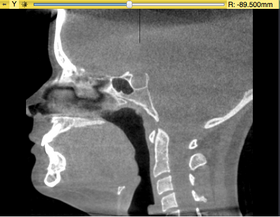

Mask Creation

Input Scan to be masked

Input mask single label segmentation

Output Scan masked